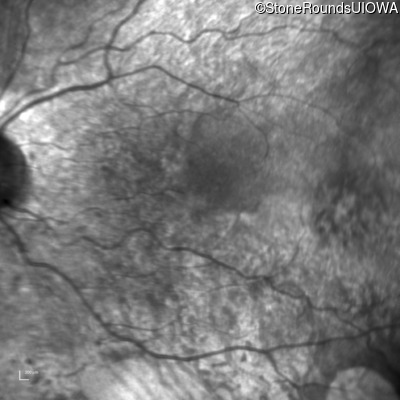

Infrared Fundus Photograph - Right - 20/63 +1

Exemplar